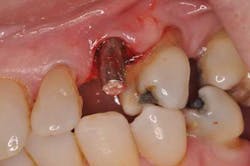

Fig. 2: Moderate bleeding noted around prefabricated abutment after crown is removed.

Looks like the original restorative dentist never fully seated the abutment! Perhaps that would explain why the patient believed the crown “never felt right.” We remove the abutment and see that there are no restorative margins to speak of, just a standard, prefabricated abutment that was used right out of the package. Since there is no sign of radiographic bone loss, the gingival erythema is diagnosed as peri-implant mucositis.